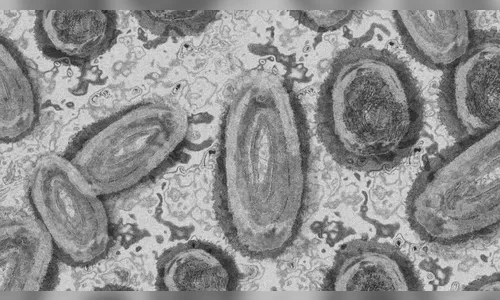

Saúde confirma 1º caso de varíola dos macacos em Paranavaí

A Secretaria de Saúde de Paranavaí, noroeste do Paraná, confirmou neste sábado (20) o primeiro caso de varíola dos macacos na cidade. O paciente é um homem de 39 anos.